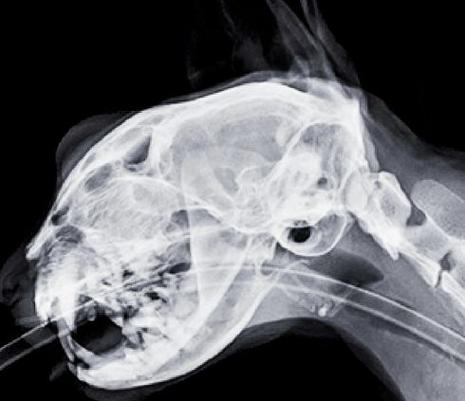

〖贰〗、如果猫咪已经因为吃排骨而呕吐,主人应该暂停喂食,并观察猫咪的症状是否有所缓解。如果呕吐持续不断或伴有其他严重症状,应及时带猫咪去宠物医院进行检查和治疗。医生可能会根据猫咪的具体情况采取拍片、手术等措施来取出卡在消化道内的骨头,并给予相应的药物治疗来缓解猫咪的不适症状。